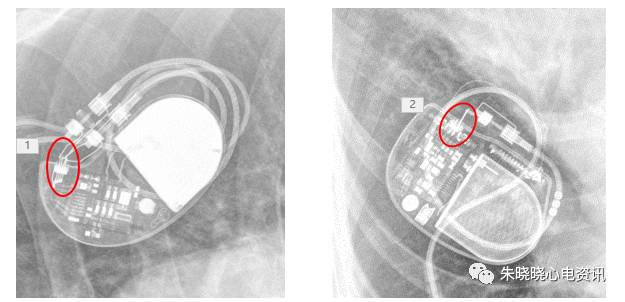

如圣犹达起搏器典型的接线方式是独有的一个长方形线圈(图8),

图8 圣犹达起搏器

百多力起搏器怎么样通过胸片识别起搏器的简易三步法_https://www.jmylbn.com_新闻资讯_第11张

图9 波士顿科学起搏器

百多力起搏器怎么样通过胸片识别起搏器的简易三步法_https://www.jmylbn.com_新闻资讯_第12张